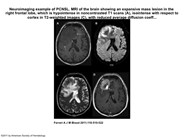

Neuroimaging example of PCNSL. MRI of the brain showing an expansive mass lesion in the right frontal lobe, which is hypointense in noncontrasted T1 scans (A), isointense with respect to cortex in T2-weighted images (C), with reduced average diffusion coefficient (B), and homogeneous contrast enhancement in contrasted T1 weighted scans (D arrows). Lesion is surrounded by modest edema (A arrows). CT and MRI findings are attributed to the high cell density and scant cytoplasm. Enhancement along the Virchow-Robin spaces, although not constant, is a highly specific feature of PCNSL.